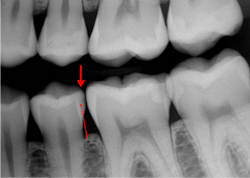

The following procedures are suggested for all classifications of resin-based composite use. The most popular burs for typical initial class I and class II restorations are #330 for the isthmus width of a molar and #329 for the isthmus width of a premolar or diamond rotary instruments of similar size and shape (figures 1 and 2).

Normal depth tooth preparation. After making the tooth preparation, etch it using your preferred procedure (total etch, selective etch, or self-etch). I prefer selective enamel etch of enamel only, but any of the three ways works. Etch 15 seconds in a nonfluoride area, or 20 seconds in a geographic area with community water fluoridation (figures 3 and 4).

Deep tooth preparation, no pulp exposure. An indirect pulp cap is indicated. Prepare the peripheral areas of the prep first, leaving the deep caries for later to avoid pulpal contamination if a pulp exposure occurs. After removing the deep caries and not having a pulp exposure, acid etch the entire prep, place glutaraldehyde as above followed by a 1 mm thick insulating bioactive liner on the deepest areas. Proven bioactive products are MTA Flow from Ultradent, Vitrebond Plus from Solventum (3M), Fuji Lining Cement from GC America, and others.